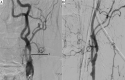

The A.N. Kazantsev artery is a vessel starting from the common carotid artery with subsequent bifurcation into 2 vessels of equal size-the internal carotid artery (ICA) and the persistent embryonic hypoglossal artery (PEHA). Until now, this artery has been considered as the ICA. However, according to all existing classifications, the ICA in the cervical segment does not have arterial branches. In addition, in view of the comparable sizes of PEHA and ICA, PEHA itself cannot be considered a branch of the ICA. Thus, by the right of the first description, the authors of the article named this vascular formation as the A.N. Kazantsev artery, which forms a bifurcation of the PEHA and ICA. In this clinical case, carotid angioplasty (CAS) was performed with stenting of 80% stenosis of the A.N. Kazantsev artery in the most acute period of acute cerebrovascular accident (ACV). According to angiography, the following was also revealed: the presence of PEHA, extending from the A.N. Kazantsev artery 5 cm above its mouth, connecting with the main artery; stenosis of the right vertebral artery 60% at the mouth; hypoplastic left vertebral artery with aplasia of the V4 segment; open circle of Willis (VC): absence of both posterior communicating arteries (PCA). Due to the high risk of recurrent CVA due to clamping of the A.N. Kazantsev artery during CEA, a multidisciplinary consultation decided to implement an emergency CAS of the A.N. Kazantsev artery. The distal embolism protection system FilterWire was inserted into the proximal part of the basilar artery through the radial artery on the left. The distal embolism protection system RX Accunet was inserted into the distal parts of the left ICA through the left common femoral artery. According to Seldinger, an Acculink stent 7-10 × 30 mm was inserted into the affected area of the A.N. Kazantsev artery, positioned and opened. The postoperative period was uneventful. ACV did not recur. Conducted dual antiplatelet therapy (acetylsalicylic acid 125 mg in the afternoon + clopidogrel 75 mg in the morning). The patient was discharged from the institution on the 10th day after the operation in a satisfactory condition.